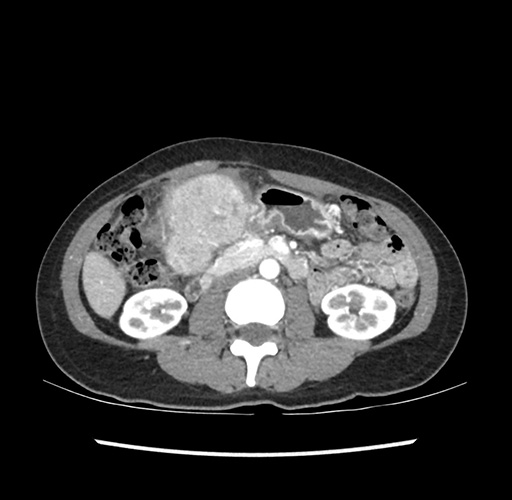

Imaging Analysis

Look through the patient's CT scan to identify any areas of concern for the necessary procedure.

Based on your CT findings, which issue(s) would give reason for "planned slowing down moment(s)" in this case?

Considering a standard left lateral sectionectomy procedure, what step(s) of the operation would you do differently in this case ?